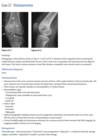

An anteroposterior view of the pelvis

(Fig. 2.24.1) in an elderly man shows extensive thick-

ening of the right iliopectineal line (arrows) with

coarsening of the trabecular pattern and increased

sclerosis throughout the entire right hemipelvis.

Paget disease (i.e., osteitis deformans)

disordered bone

remodeling affecting osteoblastic and osteoclastic

activity. Osseous involvement may be monostotic

or polyostotic, and 80% of the patients are asymp-

tomatic at the time of the discovery of the disease,

usually as an incidental finding on radiography or

because of elevated serum alkaline phosphatase and

elevated serum and urinary hydroxyproline.

stage I (acute phase), active and unbalanced osteo-

clastic bone resorption usually causes areas of lytic

bone destruction. In stage II (intermediate phase),

increased osteoblastic activity results in thickening of the cortex, coarsening of the trabecular pattern,

generalized bone overgrowth, and loss of corticome-

dullary differentiation. In stage III (late or inactive

phase), there is a diffuse increase in the density of

involved bone. Stage IV is the superimposed malig-

nant degeneration of Paget disease into a osteosarcoma.

radiographic findings in the acute phase are

osteoporosis circumscripta, in which an advancing

lytic area is seen in the frontal or occipital regions of

the skull, and subarticular osteolysis in the diaphy-

ses of the tubular bones, especially the tibia, yield-

ing a flame-shaped or “blade-of-grass” appearance

(Fig. 2.24.2). In the intermediate stage, there may

be bowing of the long bones, an “ivory” or “pic-

ture frame” vertebral body (Fig. 2.24.3), and more

extensive calvarial osteosclerosis superimposed on

a background of osteolysis, resulting in the cotton-

wool appearance of the skull.

In the long bones of the lower extremity, corti-

cal thickening, increased trabecular coarseness, and

bowing can be seen (Fig. 2.24.5), and CT can confirm

these findings (Fig. 2.24.6).

MRI can be used to detect malignant sarcomatous de-

generation by showing new bone destruction, soft-

tissue masses, and bone and soft-tissue edema.